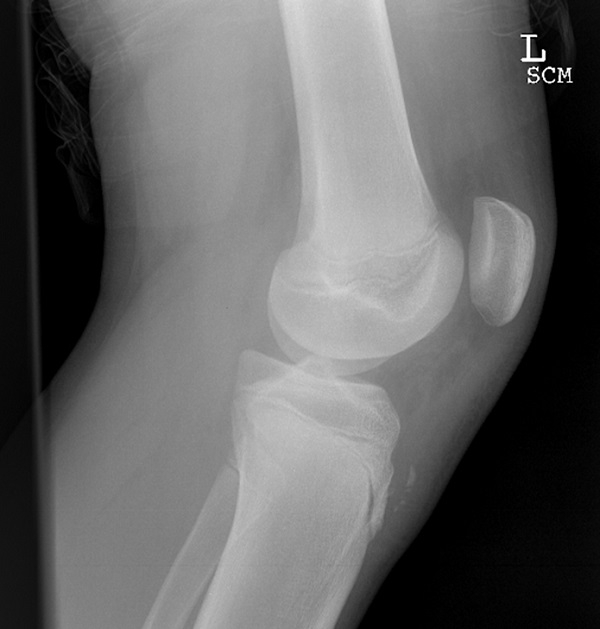

Osgood Schlatter

Osgood-Schlatter disease is a common cause of knee pain, particularly in adolescent male athletes. During early adolescence (typically ages 13-14 for affected males, and ages 10-11 for affected females), there are periods of rapid growth in which the quadriceps tendon puts traction on the apophysis of the tibial tubercle where the patellar tendon inserts. This traction apophysitis is worsened by sports that involve repetitive running, jumping, or kneeling, and it improves with rest. Approximately one fourth of affected individuals have bilateral disease. On physical examination, there is edema and tenderness over the tibial tubercle. A firm mass can sometimes be felt due to heterotopic bone formation. Pain can be reproduced by extending the knee against resistance. Radiographic findings are nonspecific and include anterior soft tissue swelling, lifting of tubercle from the shaft, and irregularity or fragmentation of the tubercle. Treatment consists of activity restriction, stretching exercises, and non-steroidal anti-inflammatory medications.